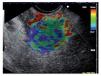

Representative areas from the mass (A) and soft reference areas (B) are analyzed. The result of the elastographic evaluation is defined by the quotient B/A (strain ratio). In Figure 6 a ratio-elastography of a pancreatic cancer is shown (ratio=25.27).

Figure 6. A ratio-elastography is shown. The ratio between measures in the small circle of normal tissue (A) and cancer tissue in the big circle (B) is over 10 (ratio=25.27).